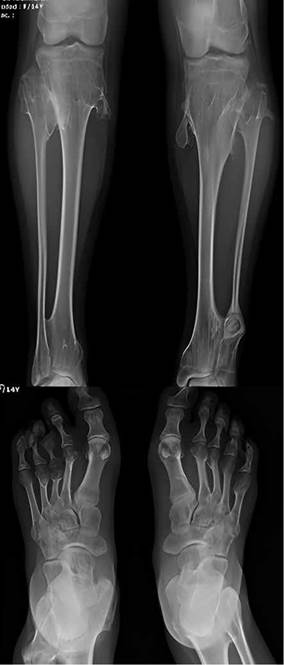

Fuente: Cortesía del Dr. Ledezma, CEMED.

Figura 3:

(C) Proyección AP de fémur izquierdo muestra una exostosis sésil en borde lateral de extremo proximal y dos exostosis pediculadas que surgen de la región metadiafisiaria distal.

(D) Proyección AP de fémur derecho muestra espacio articular coxofemoral incrementado en altura en relación con una subluxación articular, ángulo cérvico diafisario de 150 grados (coxa valga), exostosis pediculada en epífisis distal.

Figura 4:

(E) Proyección AP de ambas piernas muestra múltiples exostosis sésiles y pediculadas que surgen de las regiones metadiafisiarias femoral, tibial y peronea de forma bilateral.

(F) Proyección AP de ambos pies muestra lesiones líticas intramedulares ligeramente expansivas (los más representativos localizados en el extremo distal del tercer y cuarto metatarsiano derecho), además de acortamiento del tercer metatarsiano derecho. Exostosis sésiles en extremo proximal de la 2da falange proximal derecha y la 4ta falange proximal izquierda.

Proyección oblicua de pie izquierdo muestra exostosis pediculada que se origina de región metafisiaria de la tibia produciendo un efecto de masa que comprime el extremo distal del peroné deformando su estructura, además de dos lesiones líticas en cabeza del tercer y cuarto metatarsiano.